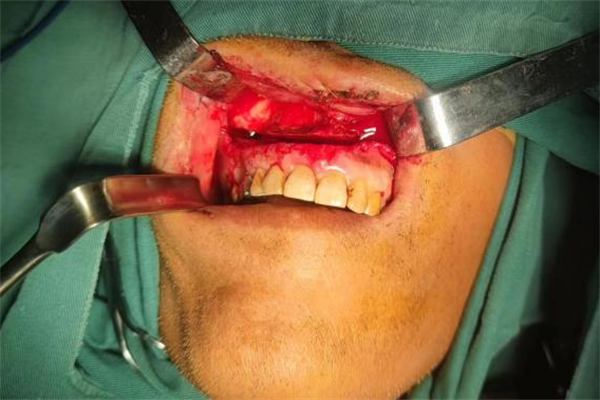

李萬東副主任醫(yī)師給予患者局部麻醉,探查后發(fā)現(xiàn)情況遠比想象的要更嚴重?;颊哂覀让娌看竺娣e電鋸切割傷,且邊緣不規(guī)則,腮腺損傷,部分咀嚼肌肌腱斷裂,多支動靜脈斷裂,上頜骨Lefort I型骨折,延伸至右側上頜竇前壁完全破裂,上下頜已無法正常咬合。第一時間趕到手術室的楊濤主任立即與李萬東副主任醫(yī)師、蘆志方醫(yī)師及王可醫(yī)生組成緊急救治小組,共同參與患者的手術搶救。

經過將近1個小時的緊張?zhí)幚?,患者口內及口外大面積的電鋸切割傷口得到了妥善處置,生命體征平穩(wěn),現(xiàn)已轉入普通病房觀察。

翌日,患者生命體征平穩(wěn)后,楊濤主任又在全麻下為患者進行了上頜骨骨折切開復位內固定術,很好的恢復了患者的咬合功能和面部外形,提高了患者的生活質量。